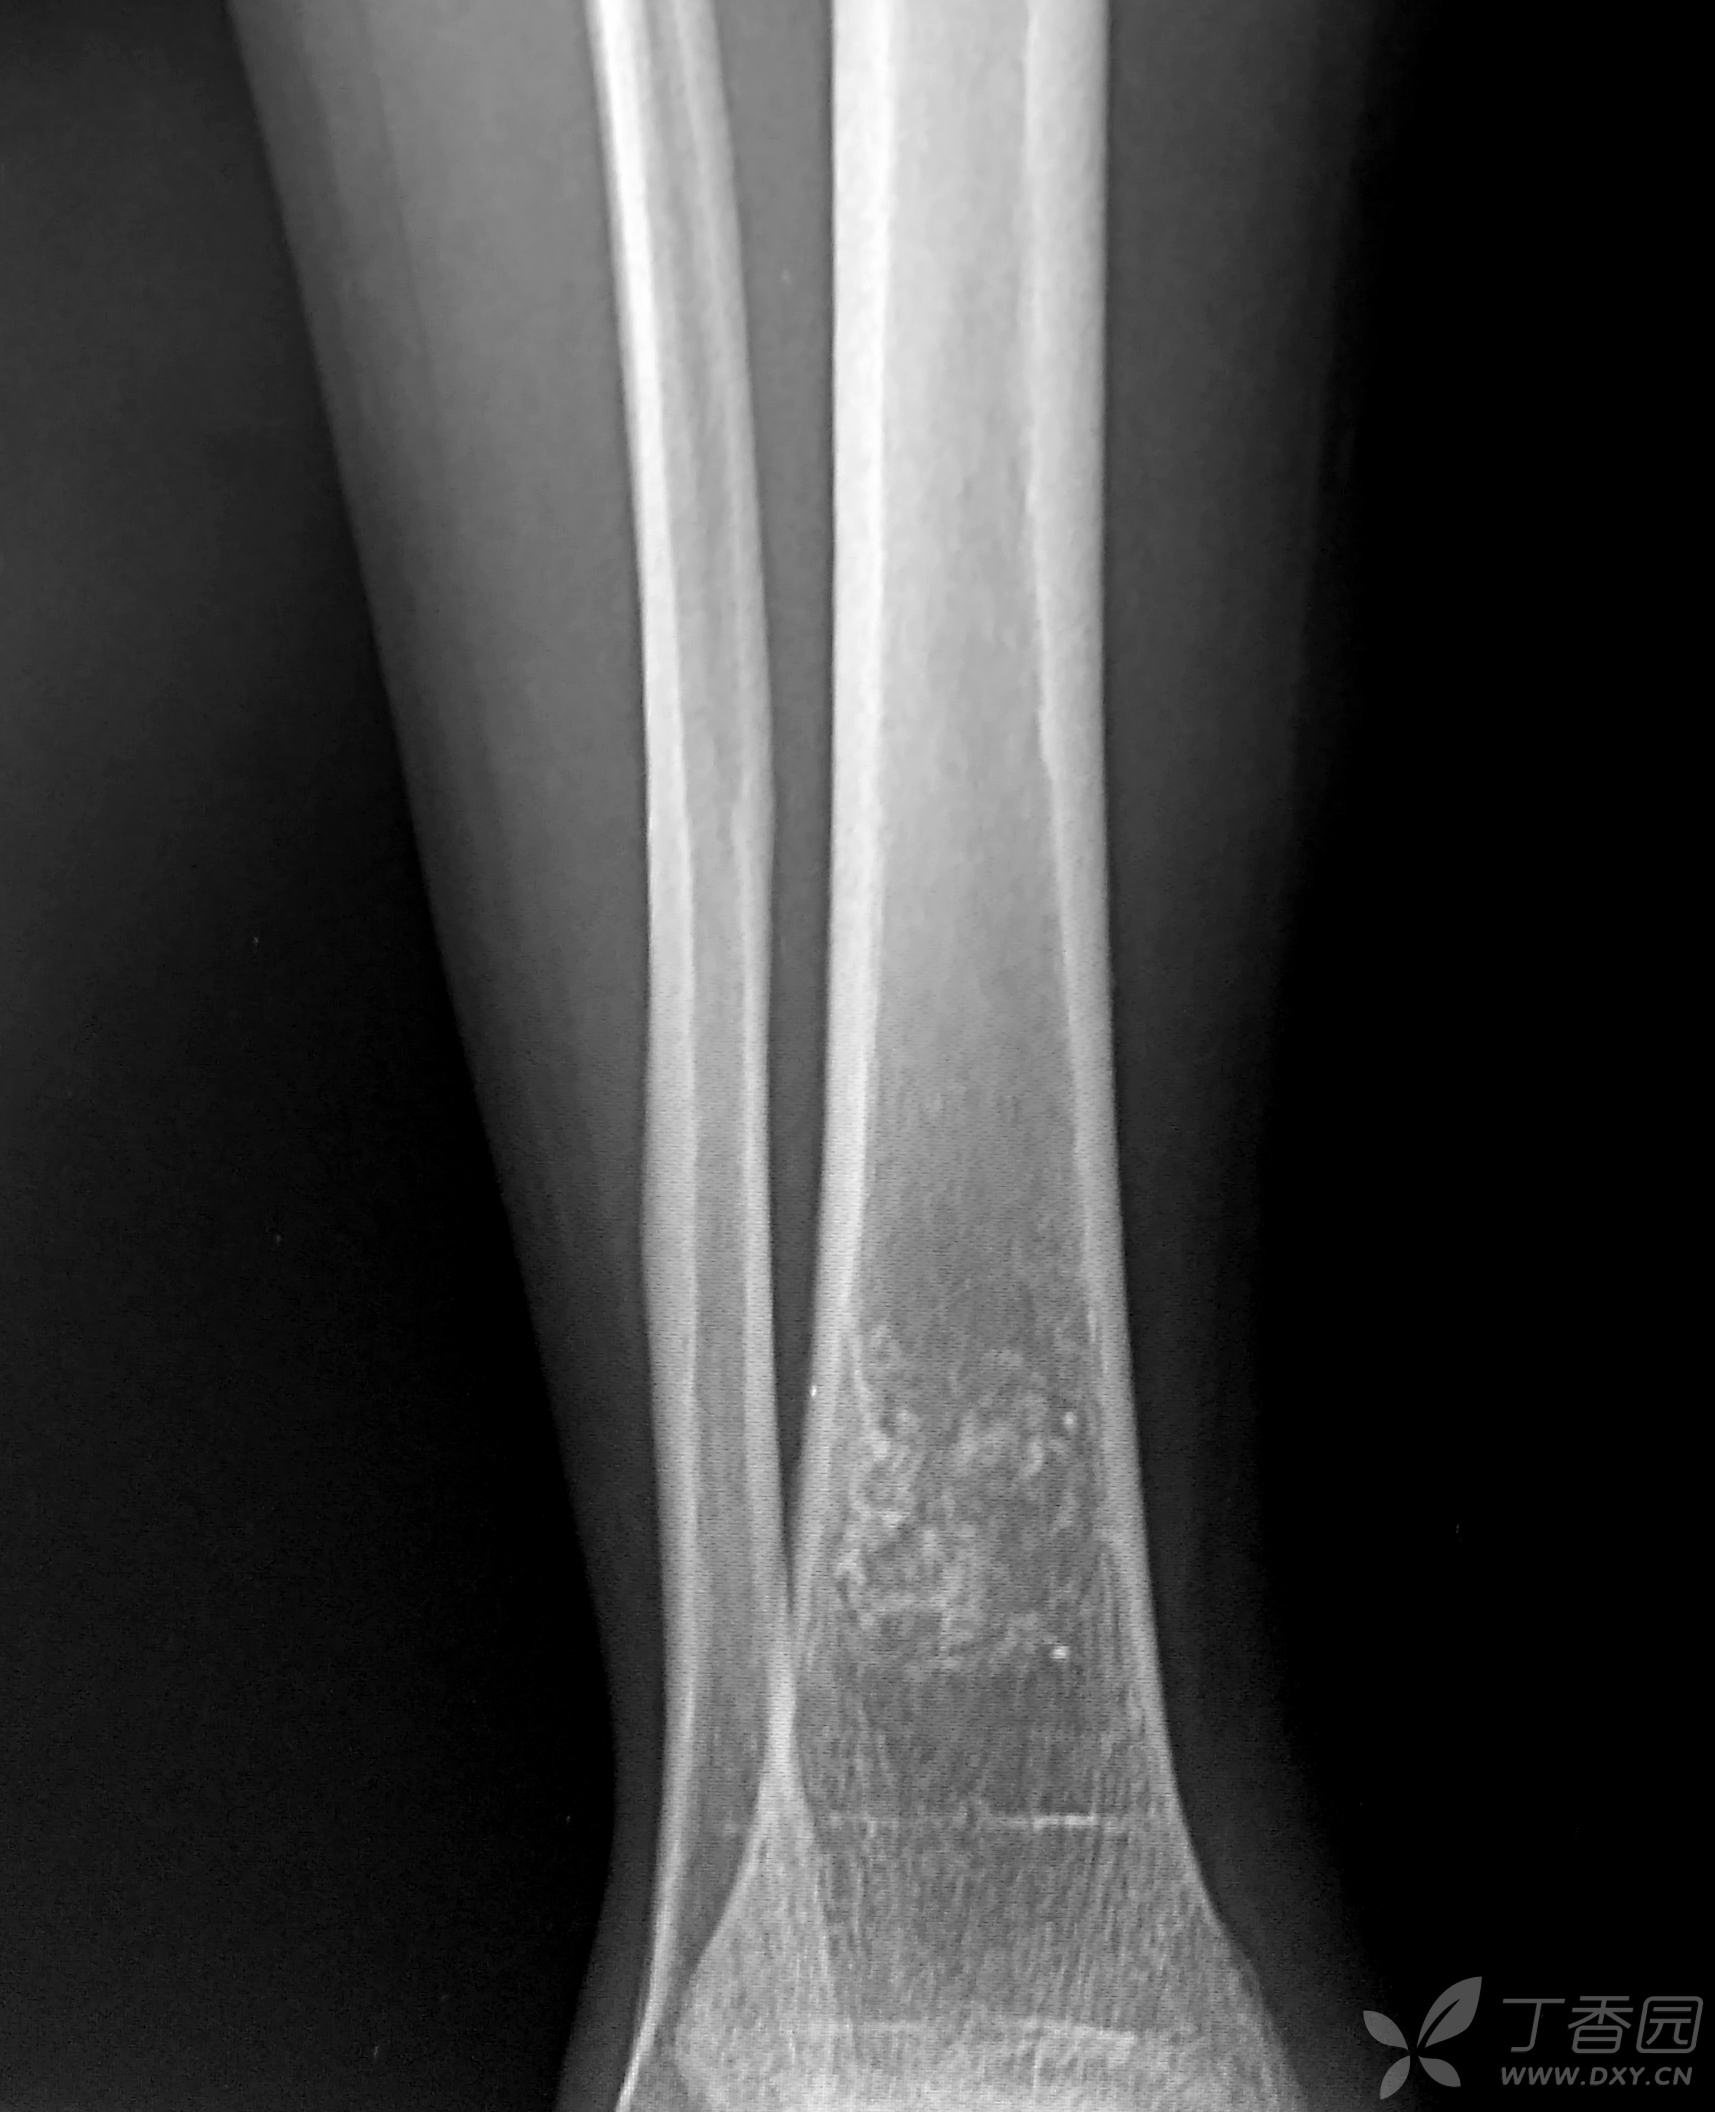

胫端下端骨质异常大家讨论骨梗死

图片尺寸976x808

骨梗死的x片,比较少见哦